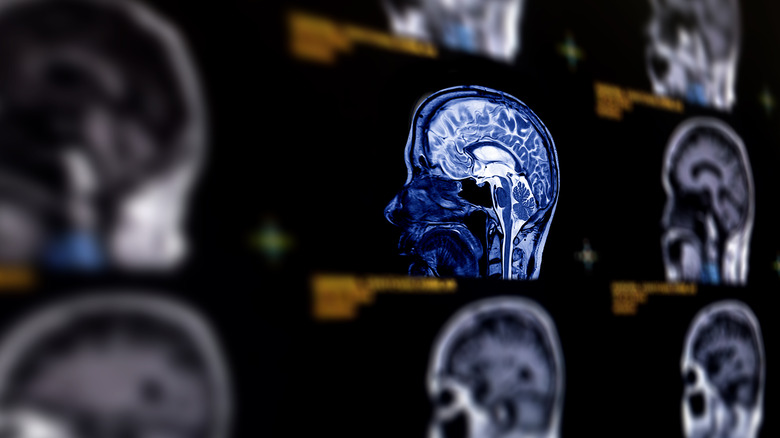

Spaceflight associated neuro-ocular syndrome (SANS)

Congratulations, you've made it to space; and you've recovered from your short bout of space sickness. What's next? There's a good chance you'll experience spaceflight-associated neuro-ocular syndrome or SANS. Most of the time, during a typical space mission — whether orbiting the Earth or traveling to the Moon — passengers experience weightlessness. Technically, gravity never stops acting on space travelers, but the spacecraft's motion cancels out this force, giving the impression of freefall. Much like in the case of space sickness, SANS is caused by prolonged weightlessness.

The human body contains a lot of fluid — the average adult is 55–60% water. On Earth, fluids are constantly pulled downward, and the body has evolved to compensate for this pull using complex networks to circulate and balance fluids from blood and lymph to bile and cerebrospinal fluid. In the presence of weightlessness, these systems have to compensate in ways not experienced during their development which can lead to health problems.

The lack of a downward pull allows more fluid to move up into the head. This increases pressure on the eyes and changes the shape and alignment of the optic nerves, retina, and the eyeball itself. As expected, this can negatively affect vision. There is also increased pressure on the brain, leading to structural changes. NASA is still studying how to combat this condition while investigating the short and long-term consequences of SANS, which occurs in about 70% of space station astronauts.